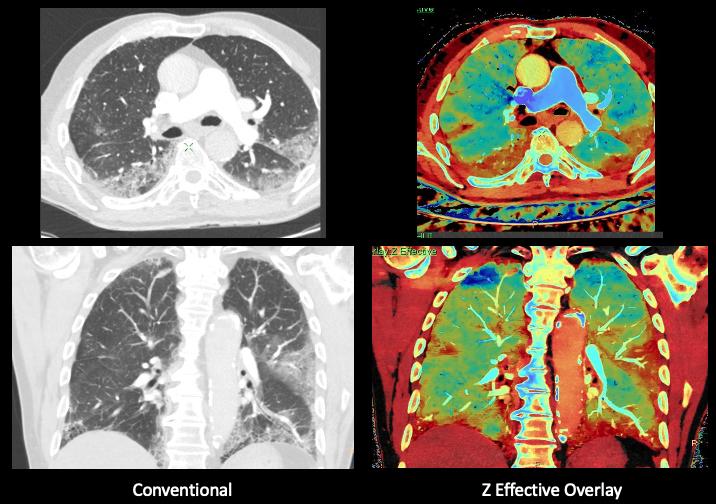

This photo gallery shows the variety of radiological presentations of COVID-19 (SARS-CoV-2) in medical imaging, including computed tomography (CT), radiograph X-rays, ultrasound, echocardiograms and magnetic resonance imaging (MRI). The radiology images show examples of typical COVID pneumonia in the lungs and the numerous complications the virus causes in the body in multiple organs, including the brain, kidneys, heart, abdomen and vascular system.